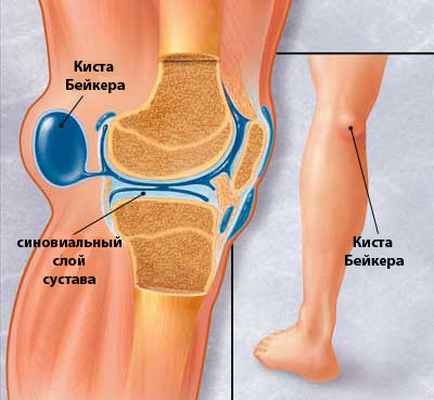

Киста Беккера – под этим термином подразумевается скопление воспалительной жидкости (не гноя) в слизистой сумке, расположенной на задней поверхности голени, чуть ниже подколенной ямки. У 50% людей эта сумка находится между сухожилиями мышц (икроножной и полуперепончатой), она сообщается с коленным суставом с помощью небольших отверстий и является вариантом нормального развития сустава.

В случае, если в коленном суставе протекает длительный воспалительный процесс, жидкость, которая образуется в результате, и скапливается в этой межсухожильной сумке и приобретает название этого заболевания. Физически, киста представляет собой припухлость с обратной стороны колена. При воспалении, в колене скапливается жидкость, которая может просочиться в эту “сумку”, тем самым увеличивая ее в размерах. Чаще всего болезнь развивается из-за обменно-дистрофических или воспалительных процессов, которые протекают в коленном суставе. Кисту Беккера вызывают патологии вроде остеоартрита, артроза, ревматоидного артрита, но возможны и другие варианты. Кроме того встречаются сложные кисты Бейкера — сросшиеся (синехии), с перегородками внутри (септы), с мелкими дочерними кисточками внутри основной.

Подколенный бурсит (киста Бейкера). Особенностью подколенной серозной сумки является то, что в половине случаев она соединяется с полостью коленного сустава, поэтому в большинстве случаев гонартрит и подколенный бурсит развиваются одновременно. Причинами первичного подколенного бурсита являются травмы, микротравмы, перегрузка коленного сустава (в частности при нарушении статики), вторичного— ревматоидный артрит, гонартроз с реактивным синовитом и другие заболевания коленного сустава.